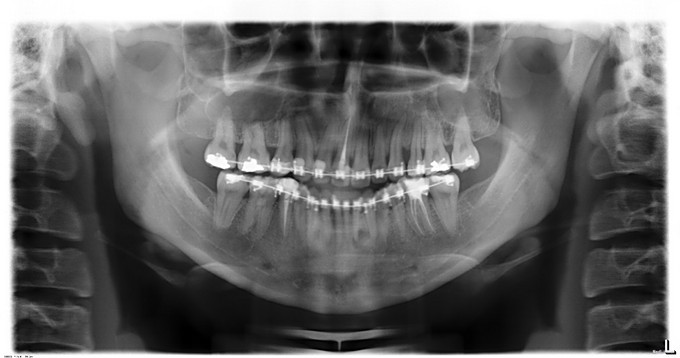

入院诊断:1.下颌前突2.上颌后缩3.偏颌畸形,出院诊断: 1.下颌前突2.上颌后缩3.偏颌畸形4.双侧上颌窦粘液囊肿,全麻下行“上颌LefortI型颌骨前徙术+骨内坚固内固定术+双侧下颌升支矢状劈开后退术+双侧下颌骨去骨皮质术+骨内坚固内固定术+双侧邻近瓣转移修复术+双侧上颌窦粘液囊肿摘除术”

现患者一般情况可,生命体征平稳,切口对位良好,缝线固定在位。经上级医师批准,予今日办理出院